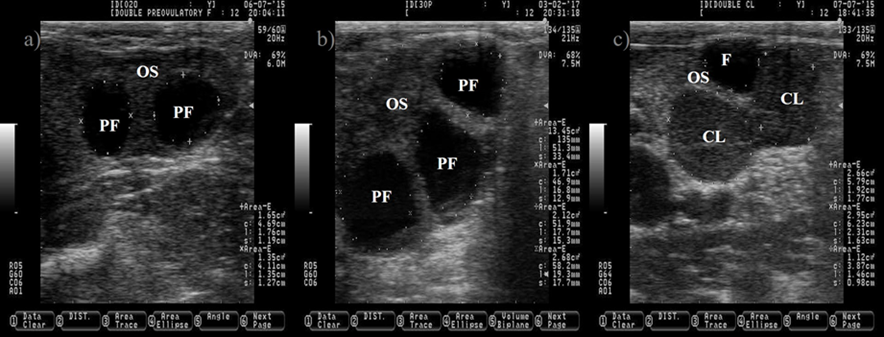

The follicular fluid is anechogenic, which make the PF appears as a dark circle. The ovulation of two PF will produce two corpora lutea (CL, c). The CL is usually darker (hypoechogenic) than the ovary stroma (OS). Pictures were taken using a 7.5 MHz probe at random stage of the estrous cycle.

Figure 2 Pictures depicting two (a) and three preovulatory follicles (PF, b) at estrus

The cow normally ovulates one follicle between 28 to 31 h after the onset of estrus16,17, but occasionally more than one follicle ovulates (Figure 2), increasing the incidence of twin pregnancies. Pregnancies carrying more than one product are undesired because it impairs reproductive performance and reduce the productive life span of the dam18. Unfortunately, the incidence of twin pregnancies has increased over the years. The improvement in nutrition, management practices and the genetic progress to increase milk production predispose to the augmented incidence of twin pregnancies19. In addition, cows carrying the Trio allele are more likely to carry twins20. Fortunately, the incidence of twin pregnancy can be prevented by ablation of multiple follicles before artificial insemination, leaving only one preovulatory follicle21.